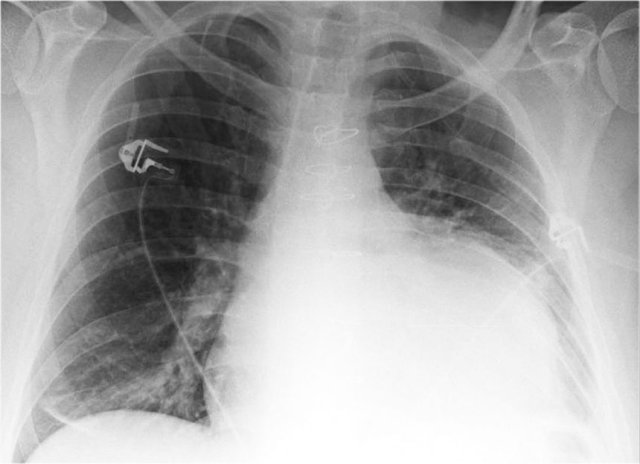

Pacemaker

There are different types of cardiac pacemakers.

Here we see a pacemaker with one lead in the right atrium and another in the right ventricle.

A third lead is seen, which is guided through the coronary sinus towards the left ventricle.

This is done in patients with asynchrone ventricular contractions.

Pacing both ventricles at the same time will lead to synchrone contractions and a better cardiac output.